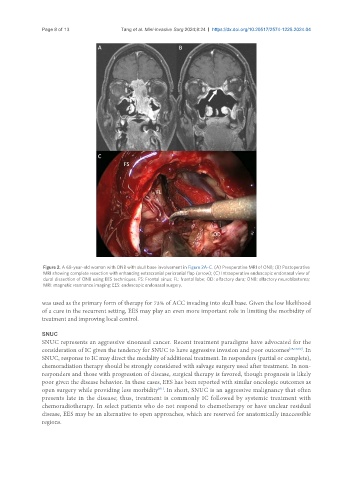

Figure 2. A 68-year-old woman with ONB with skull base involvement in Figure 2A-C. (A) Preoperative MRI of ONB; (B) Postoperative

MRI showing complete resection with enhancing extracranial pericranial flap (arrow); (C) Intraoperative endoscopic endonasal view of

dural dissection of ONB using EES techniques. FS: Frontal sinus; FL: frontal lobe; OD: olfactory dura; ONB: olfactory neuroblastoma;

MRI: magnetic resonance imaging; EES: endoscopic endonasal surgery.